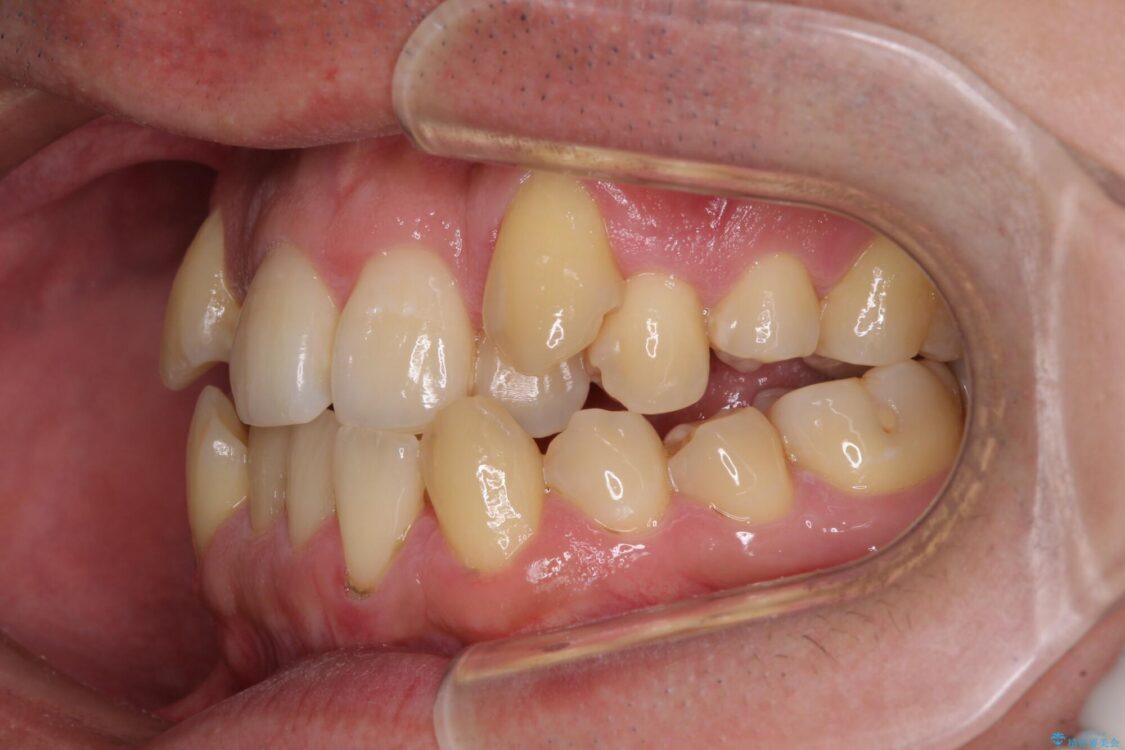

八重歯と前歯のクロスバイトを改善したいとのことで来院された患者様です。

デコボコの程度は強かったのですが、口元の突出感はなかったため、非抜歯矯正としました。

治療前

• 八重歯とクロスバイト 目立たないワイヤー装置で矯正治療 治療前画像